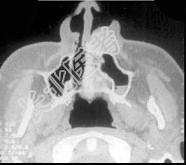

- 多项选择题面裂囊肿(影像表现如组图)包括 ( )

A、球上颌囊肿

B、鼻腭囊肿

C、正中囊肿

D、鼻唇囊肿